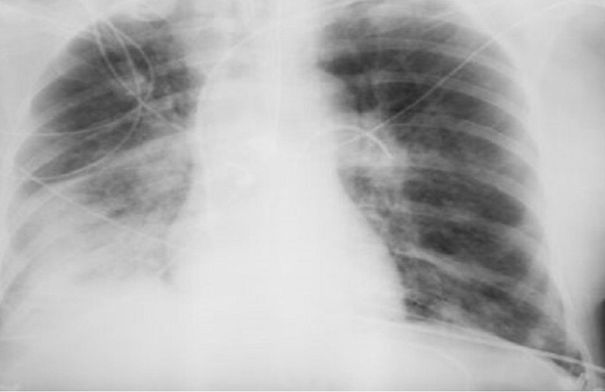

ووفقًا لها، يستخدم الإشعاع فقط في أنواع معينة من الفحوصات، ولا تتضمن جميع طرق التشخيص التعرض للإشعاع. فمثلاً، يستخدم التصوير بالموجات فوق الصوتية والتصوير بالرنين المغناطيسي، وهذه طرق آمنة تمامًا حتى للنساء الحوامل. أما الأشعة السينية فتستخدم فقط في التصوير الشعاعي، والتصوير الفلوري، والتصوير المقطعي المحوسب، بينما لا تتضمن طرق أخرى التعرض للإشعاع.

وتقول: "يمكن للنساء المرضعات الخضوع لأشعة الأسنان السينية، والتصوير الفلوري، وتصوير الثدي بالأشعة السينية بأمان. ولا يؤثر الإشعاع على حليب الثدي أو الطفل. ولكن توصف الأشعة السينية للنساء الحوامل فقط في حالات طبية صارمة، وحينها يجب حماية البطن بمئزر من الرصاص".

وبالإضافة إلى ذلك، تصدر الأجهزة الحديثة جرعات ضئيلة جدًا. أي لتلقي الإشعاع الضار، يتطلب الأمر الخضوع لمئات عمليات المسح المتتالية، وهو أمر مستحيل في الممارسة العملية. وللمقارنة، تصدر أشعة الأسنان السينية حوالي 30 ميكروسيفرت، وتصدر أشعة الفلوروغرافي (Fluorography) حوالي 500 ميكروسيفرت، وتعتبر الجرعة التي تزيد عن 50 ألف ميكروسيفرت سنويًا خطيرة.

وتؤكد بلاتونوفا أن عدم اكتشاف المرض أخطر بكثير من الخضوع للأشعة السينية، حيث تقلل المعدات الحديثة من المخاطر، كما أن الفحوصات في الوقت المناسب تسمح بالكشف السريع عن الأمراض وبدء العلاج.